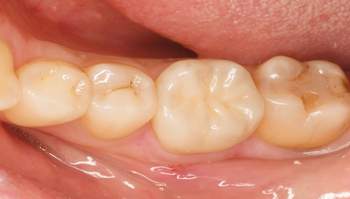

治療前

治療中

治療後

| 治療内容 | 右下6コア形成、仮歯作成、ジルコニアステイン形成 |

| 治療費 | 合計 113,300円(2022年7月現在) 仮歯 3,300円 ジルコニアステイン 110,000円 |

| 治療期間 | 1ヶ月 |

| 治療のリスク・副作用 | 仮歯の期間は仮歯が取れやすくなっている。 天然歯より硬いので噛み合う歯が欠けてしまうことがある。 |